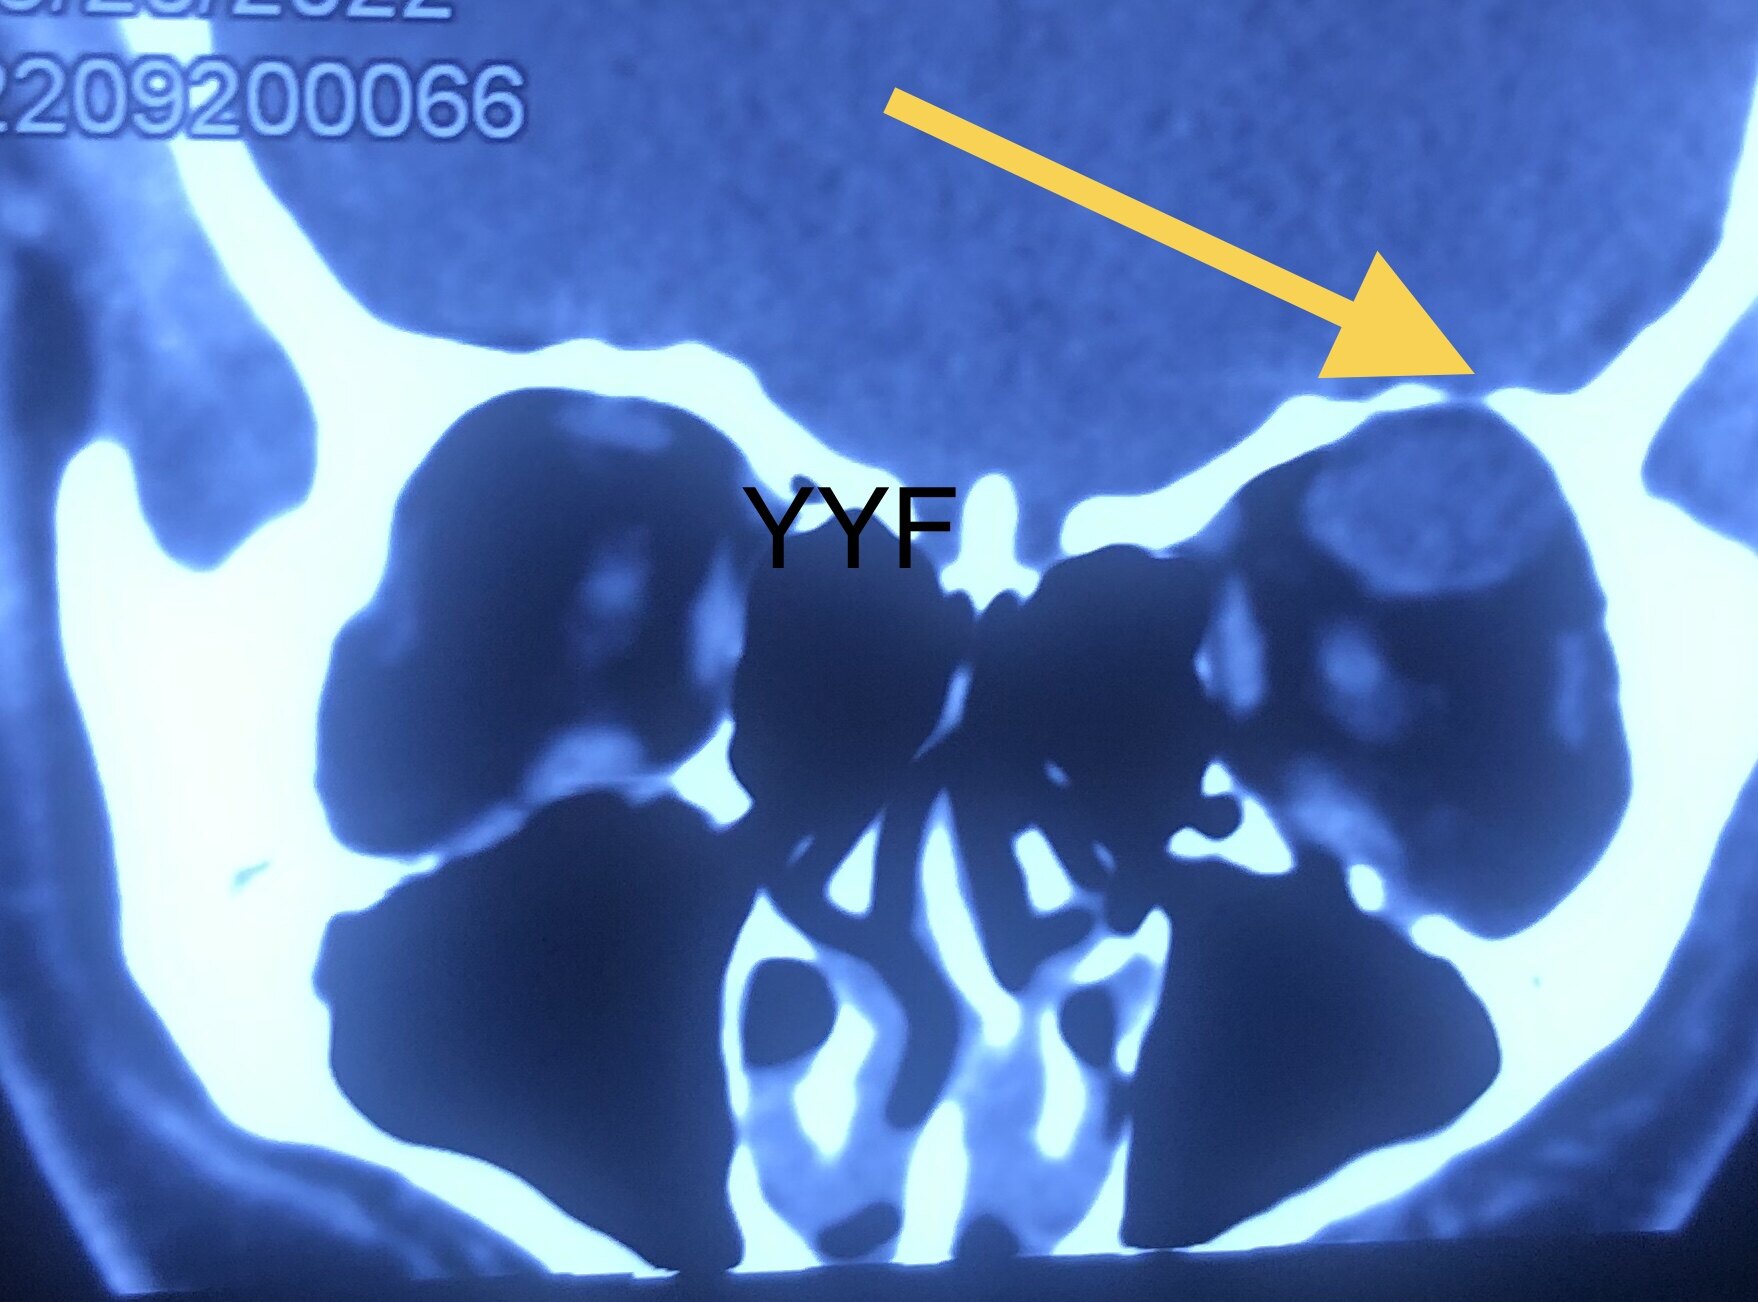

影像学显示肿物呈现不规则、结节状。

箭头处眶顶骨质压迫吸收

根据T2加权上的特殊表现首先考虑神经鞘瘤,其形态符合神经起源的肿瘤。

矢状位可以看到串珠样结节状外观及邻近结构的关系